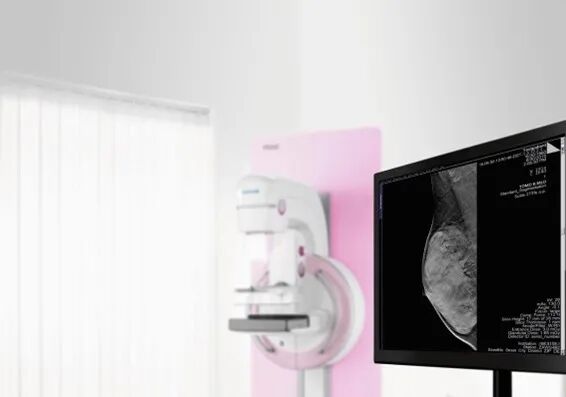

数字乳腺断层摄影(Digital Breast Tomosynthesis,DBT)作为一种三维成像技术,是指X线球管在一定的角度范围内进行多次、低剂量的曝光,获得一系列压迫后的二维乳腺影像,再将这些影像重建成平行于探测器、高分辨率的断层影像。

重建后的薄层影像可以独立或连续的方式显示。DBT的成像原理早在20世纪30年代就已出现,但直到几十年后,随着平板探测器的发展、计算机重建以及后处理算法的进步,才在乳腺X线摄影中得到飞跃发展。每个设备制造厂商的DBT技术都略有不同,主要为球管的旋转角度、曝光次数等。一般来说,X线球管的旋转角度越大,所获得的断层信息也越多,图像的分辨率也愈高。西门子医疗拥有正负25度,共50度的业内最大扫描角度。以及最薄的重建层厚,0. 2mm。随着临床应用的广泛开展,DBT已经是乳腺的常规影像检查方法,也成为了部分地区用于乳腺癌筛查的常规手段。